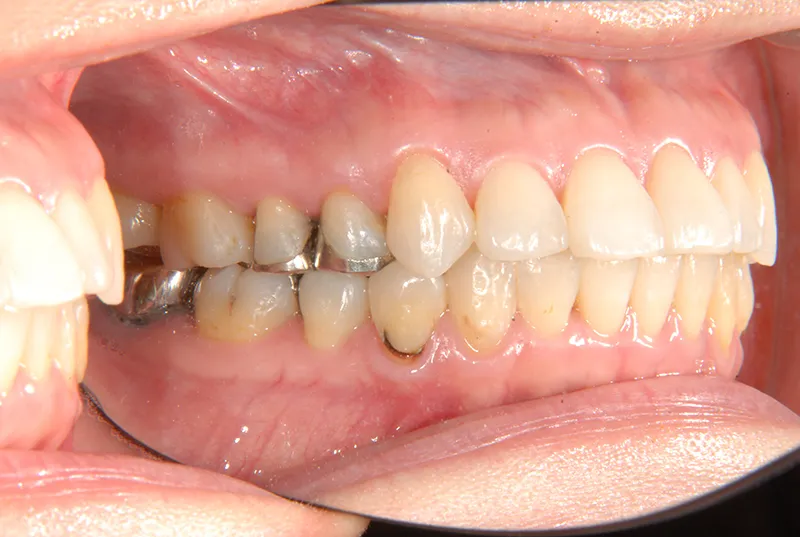

初診時年齢 40歳以上 (女性) 主訴 上下のがたがた・噛み合わない

診断名 叢生 装置名

上下のがたがたと噛み合わない事を主訴に来院されました。

歯は抜かずに矯正治療しました。

治療回数35回、2年8ヶ月の治療期間で矯正治療を終了しました。

噛み合わせが安定する事で、大きくなっていた咬筋が正常な大きさになり、顎のラインもシャープになり大変よろこばれていました。